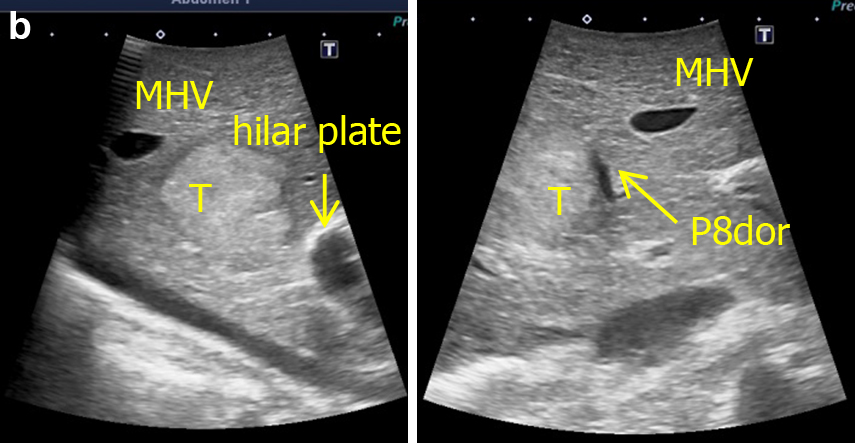

術中写真,術中超音波画像,術前シェーマを用いて,皮膚切開(本稿では省略),開腹所見(Fig. 2a),術中超音波所見(Fig. 2b),授動後(Fig. 2c),門脈染色(Fig. 2d)のパートを記載した.

d: Procedure for portal segmentation. P8dor (arrow) was punctured followed by injection of indigo-carmine solution under ultrasound-guidance. The boundaries of S8dor were identified on the liver surface (dotted line) and marked by electrocautery.